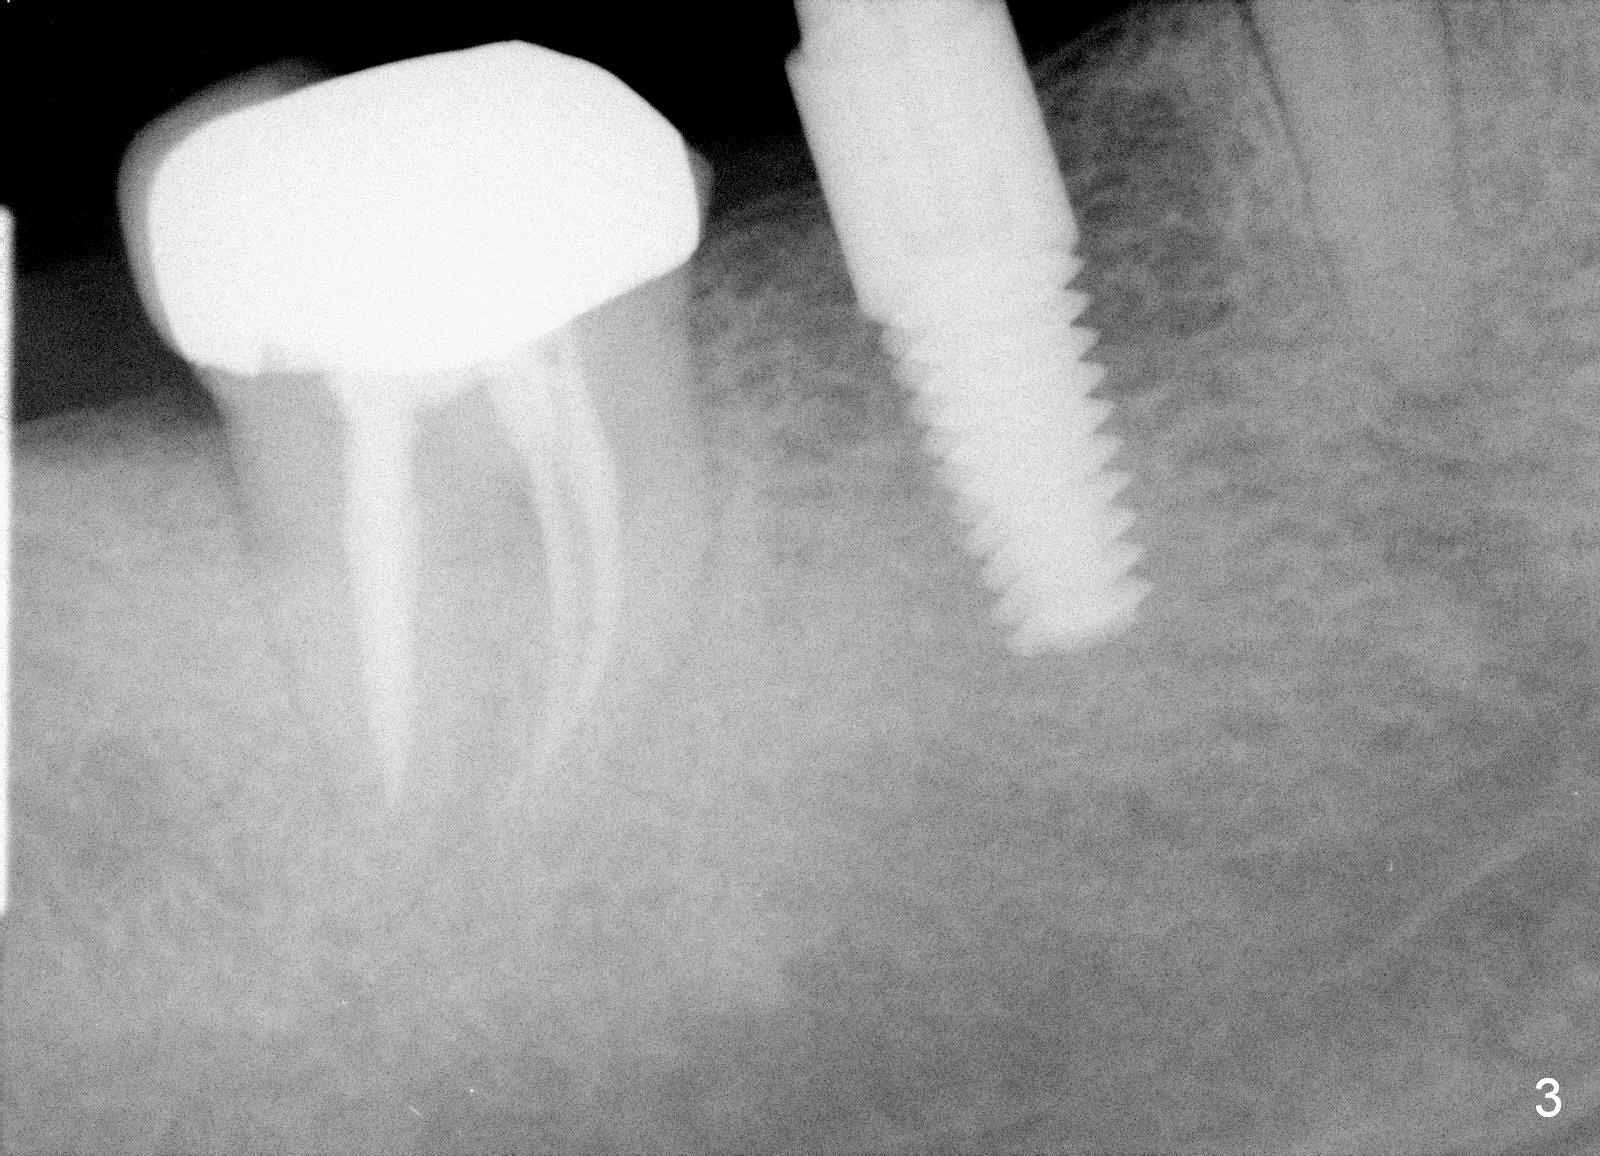

A 47-year-old man has history of bruxism, chipping porcelain from #29-31 FPD (Fig.1). Following sectioning the FPD, osteotomy is created (Fig.2: 5x14 mm drill) for placement of a 5x14 mm tissue-level implant (Fig.3,4). A 4x3 mm abutment (Fig.5 (lingual view) A) with 3 vertical slots (* for increased retention) is placed to retain periodontal dressing. The crown over the implant has dislodged 3 times over 28 months post cementation (Fig.6). It appears that the top of the abutment is too rounded. Clinical exam shows that the abutment height can be more, although the tooth #3 is supraerupted (Fig.7 (orthodontic intrusion is not indicated because of furca infection)).